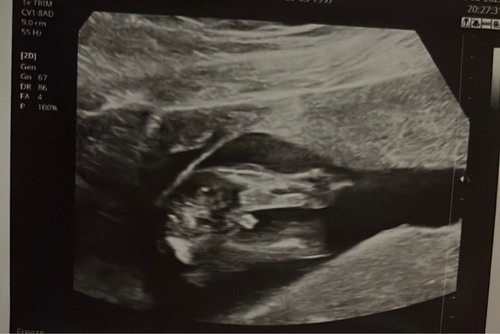

Duidelijk een meisje je ziet geen ballen. Dit is 99% de navelstreng wat toevallig lijkt op een piemeltje. Dit is van mijn zoontje hier zie je goed de ballen in beeld.